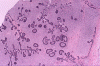

The panoramic view demonstrated a mulilocular lesion in the left ramus of the mandible. The lesion is well defined and without much sclerotic changes at the rim. The first molar is unerupted and is associated with the lesion (arrow in Panel A). On histologic section, the lesion is composed of a solid mass with numerous thin, anastomosing trabecula or cords of epithelial cells. At the and of these branching anastomosis, there the epithelial component tend to expand a little and form a small island. No larger islands are noted (Panel B and C). No calcification or eosinophilic depositions are noted in the epithelial islands. There is no microcyst formation in the epithelial component and the overall pleomophism is minimal . The embedding stroma is composed of a moderately cellular, stellate shaped, rather monotonous proliferation of cells without high grade nuclear features nor mitosis.